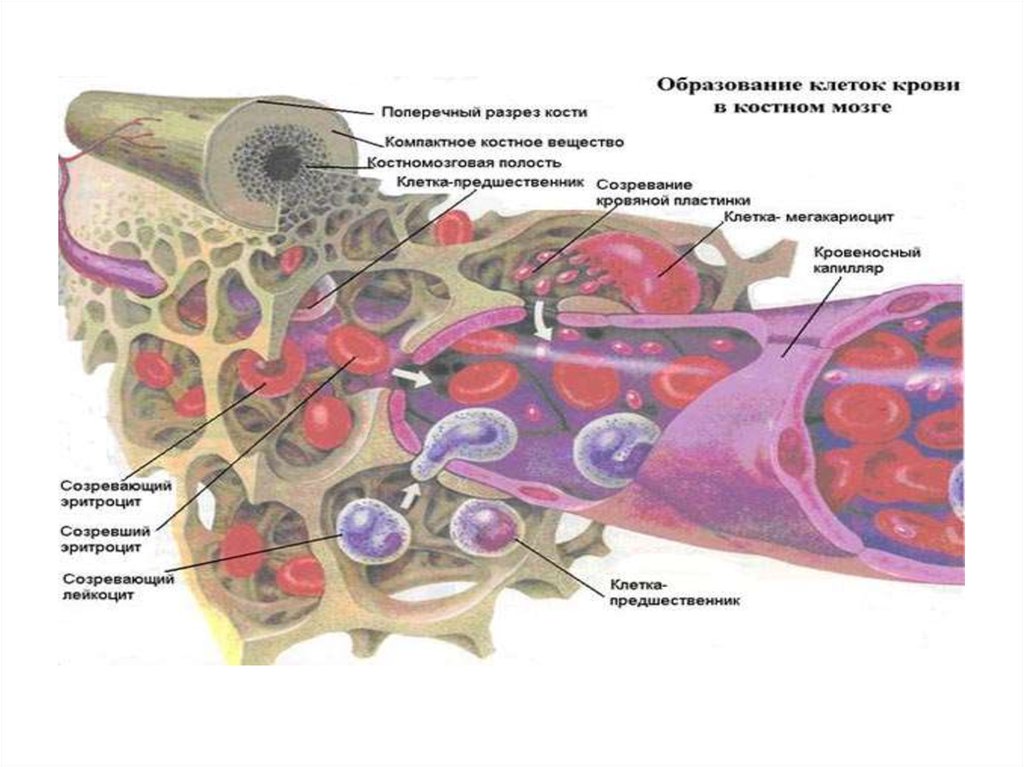

Изучение костного мозга: анатомия и функции